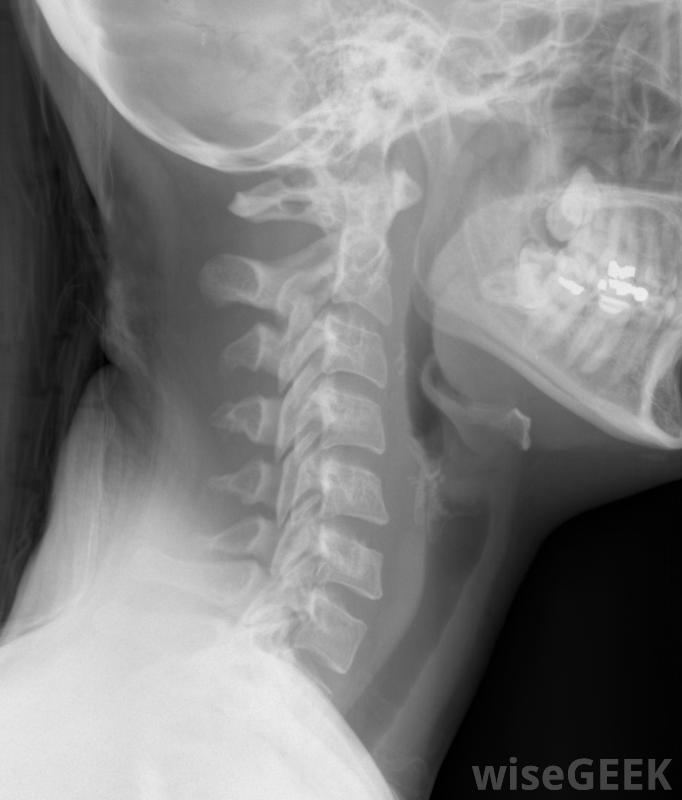

当骨头偏离正常位置时,称为半脱位。颈椎半脱位发生在颈部区域的脊椎或脊椎骨排列改变时。这种错位的骨头会对周围区域造成异常的张力,包括软组织和神经颈部(包括颈椎)的X光片。对内部结构(如肌肉、肌腱)施加的压力,颈椎半脱...

当骨头偏离正常位置时,称为半脱位。颈椎半脱位发生在颈部区域的脊椎或脊椎骨排列改变时。这种错位的骨头会对周围区域造成异常的张力,包括软组织和神经颈部(包括颈椎)的X光片。对内部结构(如肌肉、肌腱)施加的压力,颈椎半脱位引起的韧带也会引起疼痛,轻微的排列改变会引起疼痛,疼痛的范围从疼痛、压痛到紧绷,更严重的颈椎骨移位也会导致运动障碍。运动困难可能局限于颈部或全身